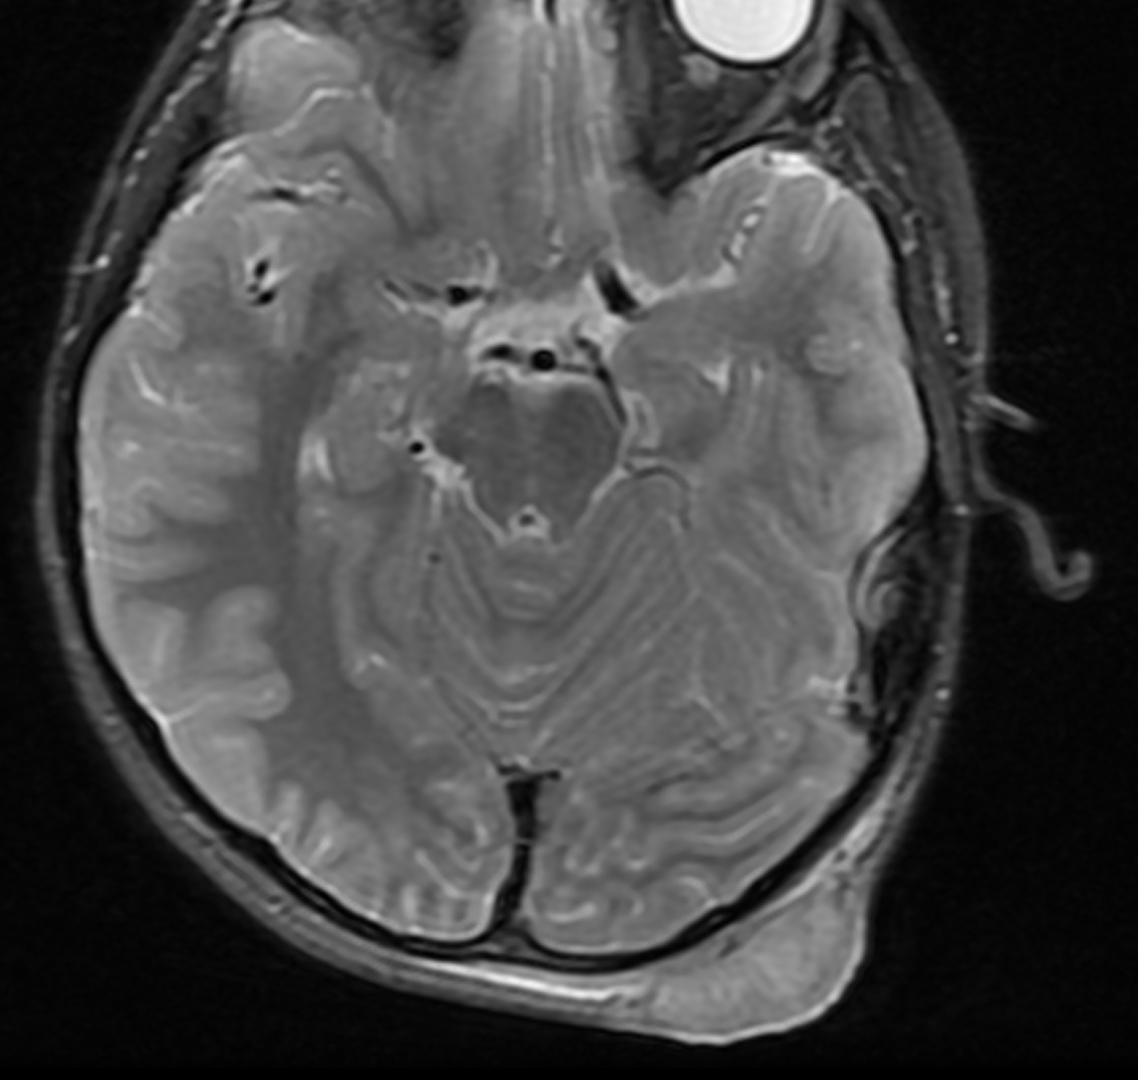

resonance imaging (MRI) with numerous ringenhancing lesions... Download Scientific Skin Lesions Mri mri findings of nodular cbccs in the head and neck regions show elliptical cutaneous lesions occurring mainly in the. superficial soft tissue masses may be classified in one of the following general diagnostic categories: mri provides high spatial and contrast resolution imaging of the skin [2, 21, 22]. the skin and subcutaneous tissues are inevitably imaged. Skin Lesions Mri.